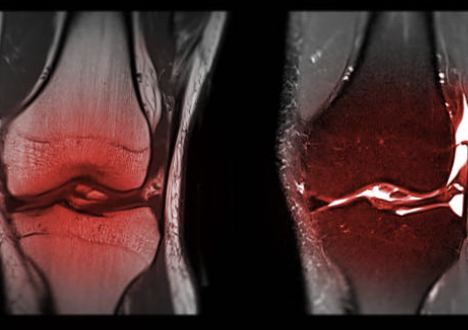

무릎 십자인대 파열 증상 및 십자인대 파열에 대해 알아보는 시간 갖도록 하겠습니다.

십자인대는 무릎 관절 내부에 있는 4개의 인대 중 하나로, 대퇴골과 승골 사이에 위치해 있습니다. 십자인대는 무릎 관절의 안정성을 유지하는 역할을 담당합니다. 무릎 관절에 직접적인 충격이 가해지거나, 무릎이 강한 스트레스를 받았을 때 십자인대가 손상되는 경우가 있습니다. 이러한 십자인대 손상은 스포츠 활동이나 사고 등으로 발생할 수 있습니다. 십자인대 손상 증상으로는 무릎 통증, 부종, 불안정감 등이 있으며, 심한 손상의 경우 수술이 필요할 수도 있습니다. 십자인대 손상을 예방하기 위해서는 적절한 스포츠화를 착용하고, 몸을 충분히 기르며, 스포츠를 할 때 안전장비를 착용하는 것이 중요합니다.

무릎 십자인대 파열은 무릎 관절 내부에 있는 십자인대 중 하나가 부분적으로 또는 완전히 파열되는 상황을 말합니다. 무릎 십자인대 파열 증상은 다양합니다. 주요 증상은 다음과 같습니다.

- 무릎 통증: 십자인대가 파열되면 무릎 주변에 통증이 나타날 수 있습니다. 통증은 가벼운 경우는 무릎 근육 주변에서 발생할 수 있고, 심한 경우는 무릎 전체에 걸쳐 나타날 수 있습니다.

- 부종: 십자인대 파열 후 부종이 발생할 수 있습니다. 부종은 통증과 함께 발생하며, 무릎이 불안정해지는 느낌이 들 수 있습니다.

- 불안정감: 십자인대 파열로 인해 무릎이 불안정해지는 경우가 있습니다. 무릎 관절에서 이상한 소리나 느낌이 들 수 있으며, 무릎을 움직이기 어려울 수 있습니다.

- 근력 감퇴: 십자인대 파열로 인해 근육 강도가 감소할 수 있습니다. 이는 무릎을 움직이기 어렵게 만들 수 있습니다.

무릎 십자인대 파열 증상은 다양합니다. 십자인대 파열이 의심될 경우 전문의와 상담하여 적절한 치료를 받는 것이 중요합니다. 치료는 초기에 치료를 받을수록 효과가 좋습니다. 또한, 파열된 십자인대의 크기와 위치, 부상의 심각성, 개인의 건강 상태 등에 따라 치료 방법과 기간이 달라질 수 있으므로, 전문의의 진단과 조언을 따르는 것이 중요합니다. 만약 치료를 제때 받지 않으면, 더 심각한 부상이 발생할 수 있으며, 무릎의 안정성이 저하되어 무릎 관절염 등의 합병증을 일으킬 수도 있습니다.